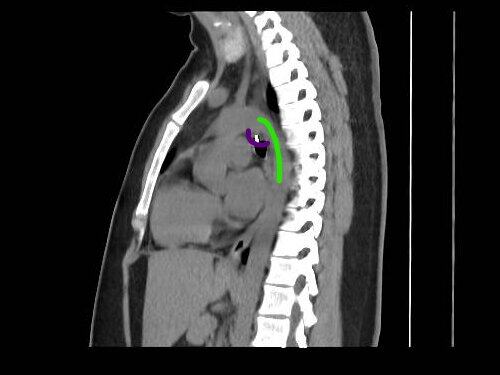

Prema pisanju medija, metalni deo nakita nalazio se svega 0,5 milimetara od aorte, što je čitavu situaciju učinilo dodatno opasnom.

Ono što je u početku trebalo da bude rutinsko vađenje stranog tela, koje bi trajalo oko 20 minuta, ubrzo se pretvorilo u mnogo komplikovaniji zahvat.

Tokom prvog pokušaja lekari nisu uspeli da pomere metalni deo, jer je on već počeo da prijanja uz unutrašnje tkivo.

„Na kraju je trajalo sat i 20 minuta, a ipak nisu mogli da ga izvade, jer se zakačio za moje telo“, rekla je, prenosi Džem pres.

Lekar šokiran koliko je metal bio blizu srca

Prema njenim rečima, i hirurg je bio zatečen time koliko se metal nalazio blizu srca. Monika tvrdi da joj je doktor tada rekao:

Ona veruje da bi, da metal nije na vreme otkriven, posledice mogle da budu kobne. Da je probio pluća ili srce, verovatno bi došlo do kolapsa pluća ili pucanja aorte.